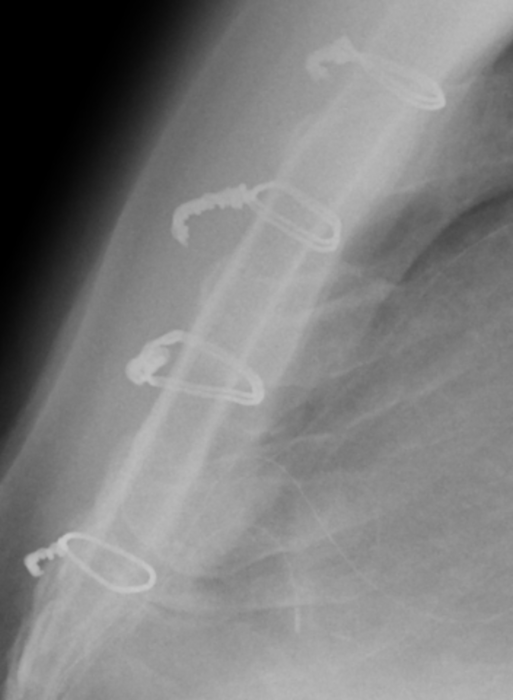

As my appointment with Dr. Abu-Omar proceeded, I learned that my assumption about the appointment was completely wrong. I learned that while it is very rare, chest pain like mine can sometimes be caused by the sternal wires that were left in my body after the surgery. (To the right I added for a second time the same X-ray photo from April 4, 2024, that clearly shows the median sternal wires, and a close-up photo taken from the June 6, 2024, CAT Scan.)

The appointment ended with a recommendation to have the sternal wires in my chest surgically removed (the wires are no longer needed, since my sternum had healed a year ago), and a promise to receive a call the next workday (Tuesday, September 3rd) with a scheduled surgery date. I was told that it was a simple, short operation (that they could slip me in between other operations). I most likely would go home the same day, but was told to be prepared to stay overnight, if needed. I was also advised that the incision from re-opening the scar area of my chest should heal in approximately two weeks.

[Friday August 30, 2024, 2:00 pm] Progress Notes Written by Yasir Abu-Omar I reviewed him at the clinic today. This gentleman underwent septal myectomy in April 2023. He had an excellent recovery with significant proved his and his symptoms. In December 2023 he developed nonspecific sharp chest pain. He has been under regular review with the cardiology team and has been seen by pain specialist. Several interventions were tried including lidocaine patches and most recently gabapentin with little help. On examination his wound appears to have healed well. Scar was somewhat hypertrophic. The sternum is completely stable. . . . presents with atypical likely musculoskeletal pain. I discussed with him the option of removal of the sternal wires in an attempt to ameliorate the pain. I told him there is no guarantee that this will work but it is worth a try. We discussed the risks and benefits and he is happy to proceed. I will schedule him in the very near future to be admitted hopefully as a day case for removal of sternal wires. Yasir Abu-Omar, MD